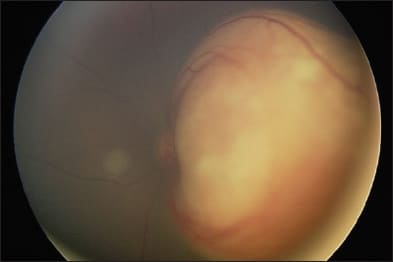

Figure 1. Left eye of a child with large macular retinoblastoma before treatment (top) and after intra-arterial melphalan and focal laser consolidation (bottom).